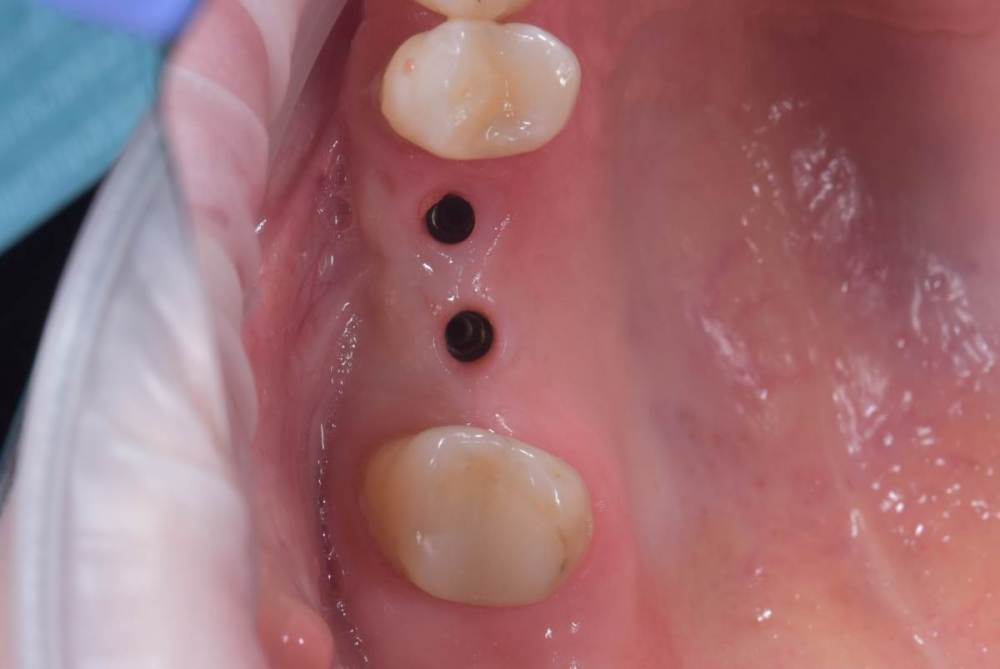

TIGER Опубликовано 8 мая, 2023 Автор Поделиться Опубликовано 8 мая, 2023 Всем привет!планировал удаление,но во время синуса решил использовать фрагмент как клин для стабилизации болта,в итоге совершил ошибку с более медиальной позицией 26,ибо шаблон не изготовил....через 5 мес одел времяхи,т.к будет тотал Ссылка на комментарий

Irouil Опубликовано 8 мая, 2023 Поделиться Опубликовано 8 мая, 2023 Вроде норм, в итоге 1 Ссылка на комментарий

TIGER Опубликовано 8 мая, 2023 Автор Поделиться Опубликовано 8 мая, 2023 @Irouil да,ортопедически всё отлично,я переживал Ссылка на комментарий